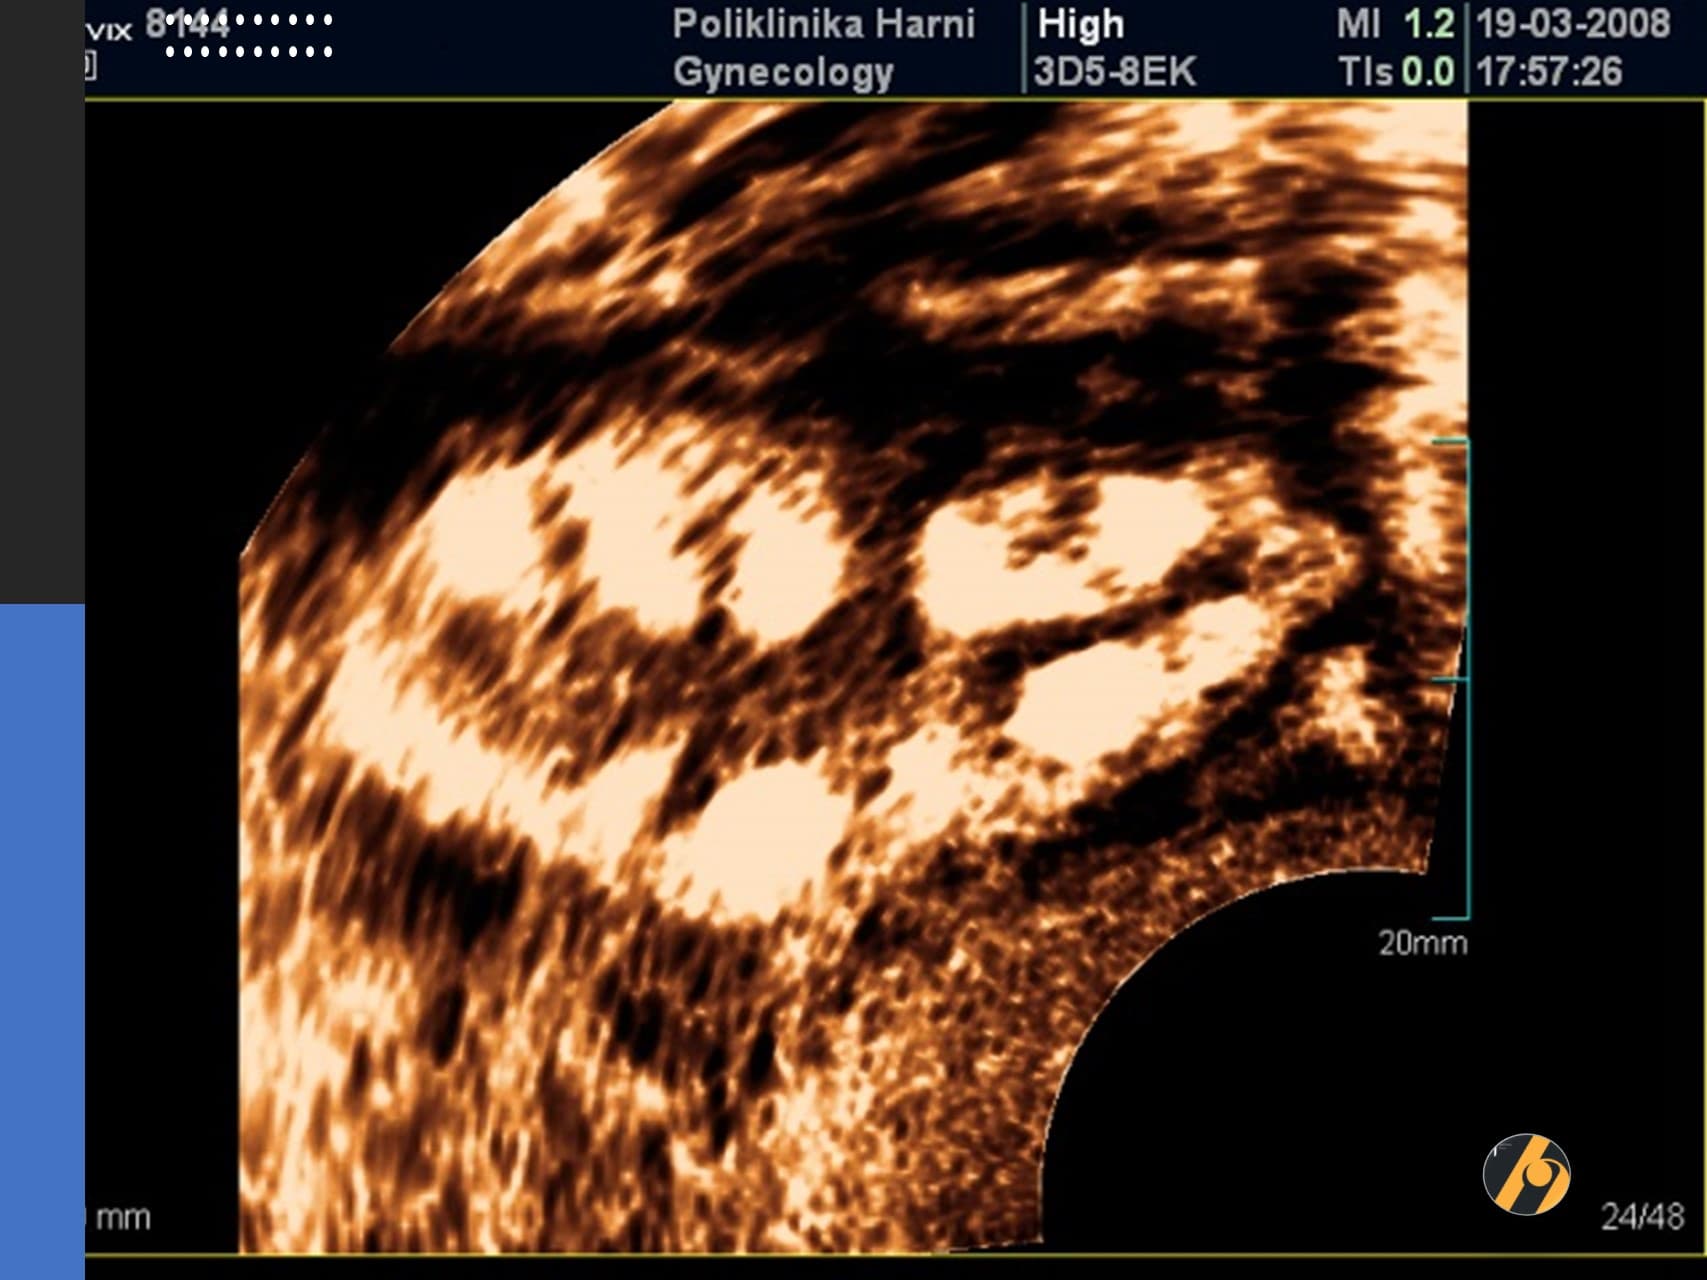

Premda su kardinalna obilježja ovog sindroma hiperandrogenizam i policističan izgled jajnika, niti jedan od pojedinačnih kriterija nije dovoljan da bi se postavila dijagnoza sindroma policističnih jajnika. Osnovna metoda u dijagnostici PCOS je ultrazvučni pregled. Koristi se transvaginalni ultrazvuk, prilikom čega se procjenjuje jesu li povećani jajnici, je li stroma - unutarnji dio jajnika koji proizvodi hormone, zadebljana, postoje li veliki broj folikula koji često tvore sliku ogrlice od perli ako su smješteni periferno ili stvaraju dojam mikrocističnosti kod difuznog rasporeda.

Dijagnoza PCOS prema Rotterdamskim kriterijima postavlja se kada žena ima najmanje dvije od sljedeće tri manifestacije: neredoviti menstrualni ciklusi ili anovulacija, povišena razina muških spolnih hormona i/ili jajnici čiji je volumen veći od 10 ml s najmanje 12 folikula na jednoj zamrznutom ultrazvučnoj slici jajnika. Nužno je isključiti ostala stanja sa sličnim znacima kao što su tumori koji stvaraju muške spolne hormone ili Cushingova bolest. Jajnici koji imaju policističan izgleda, s normalnom funkcijom i bez povišene razine muških spolnih hormona ne spadaju u sindrom policističnih jajnika i ne treba ih kao takve liječiti.

Uz ultrazvuk se u postavljanju dijagnoze PCOS koristi i niz drugih pretraga kao što su mjerenje protoka krvi kroz jajnike (kolor Dopler), određivanje bazalnog hormonskog statusauz analizu metabolizma – određivanje inzulinske rezistencije praćenjem razine glukoze i inzulina i testa opterećenja šećerom - OGTT, analiza učinkovitosti inzulina, mjerenje količine i rasporeda masnog tkiva i druge pretrage, ovisno o vodećim simptomima.